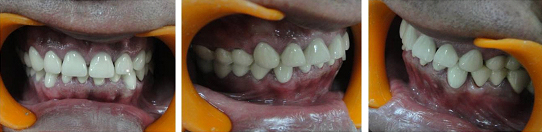

A 27-year-old male patient reported with chief complaint of discolored and severely worn maxillary and mandibular teeth and wanted to have full mouth rehabilitation. His history revealed that his deciduous dentition was normal but his permanent teeth had been discolored since eruption. Gradually over period of time, his dentition worsened. The teeth got carious, chipped and got worn off. Intraoral examination revealed severely worn dentition and reduction in axial height of clinical crowns [Table/Fig-1a,b,c]. Moderate gingivitis was present. Extra-oral examination revealed his temporomandibular joints and muscles of mastication were normal. He did not report of any parafunctional habits.

Preoperative photographs of patient